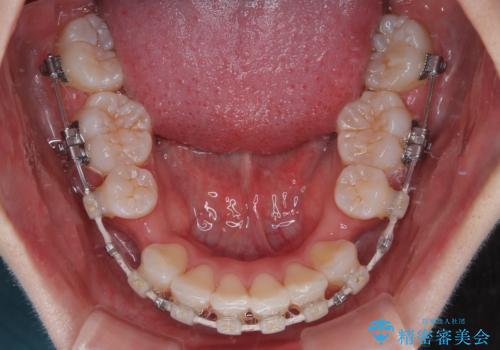

- 矯正装置

- 審美装置

- 2年

- 10-30回

下顎はデコボコが気になっていたため、上下左右第一小臼歯4本を抜去して、ワイヤー装置にて口元の突出感を改善するよう矯正治療を行うこととしました。